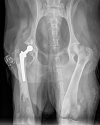

Total Hip Replacement in Dogs

Hind limb (back leg) lameness is a common reason small animal patients present to a veterinary surgeon. This is a more frequent scenario in dogs but we also see cats with this type of lameness. The causes of hind limb lameness are varied, but hip pain is a frequent reason for our patients to become […]